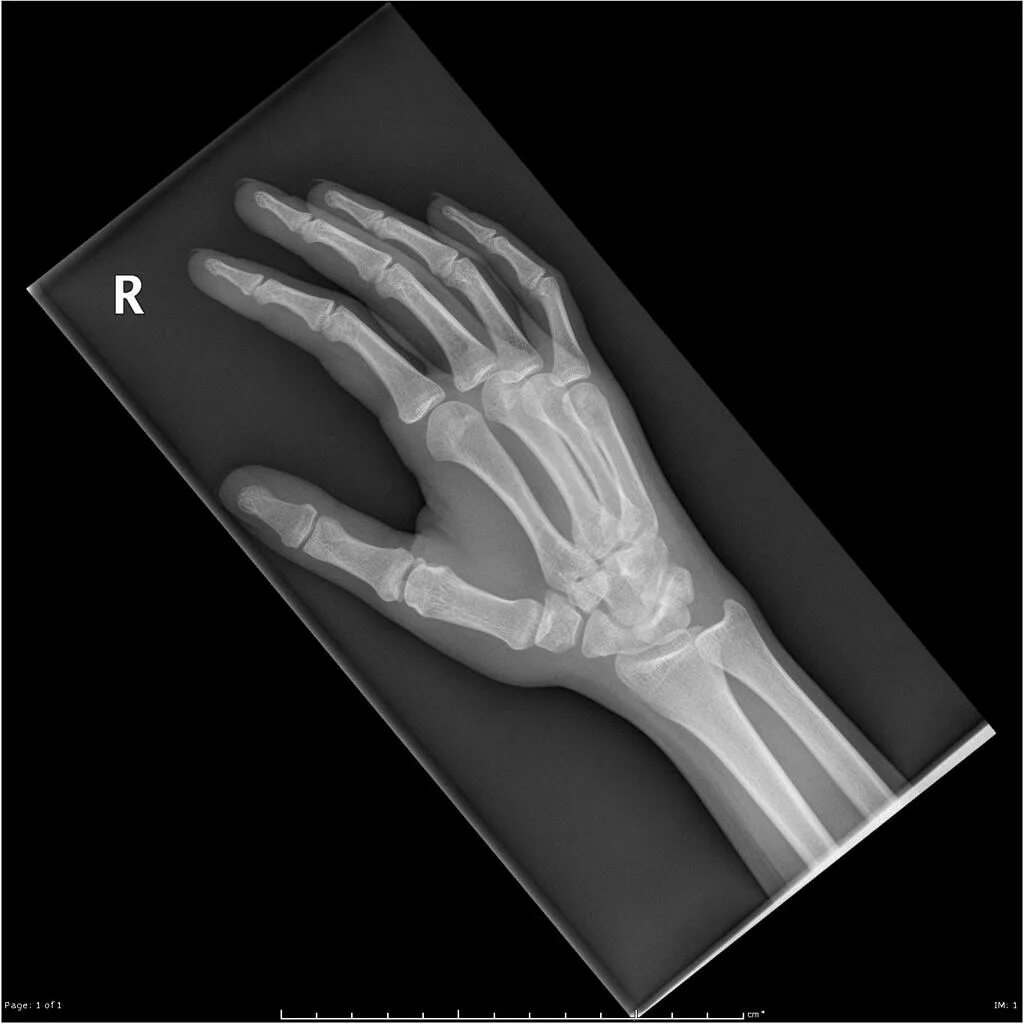

Source x rays